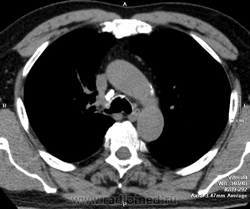

В процессе описания возникли сомнения о природе образования решили дообследовать - динамика на след день (Единичный очаг в н/д слева был и ранее. У больного сильный влажный кашель и обильное отхождение мокроты, вот такие вот дела.

Я правильно понимаю, что эндобронхиальных образований минимум 2?

Вношу ясность: тут два исследования - первое исследование сделано в понедельник, второе во вторник - в просвете бронха имеет место что то симулирующее tr, что было на верхней стенке, а затем переместилось на нижнюю за сутки - слизь.